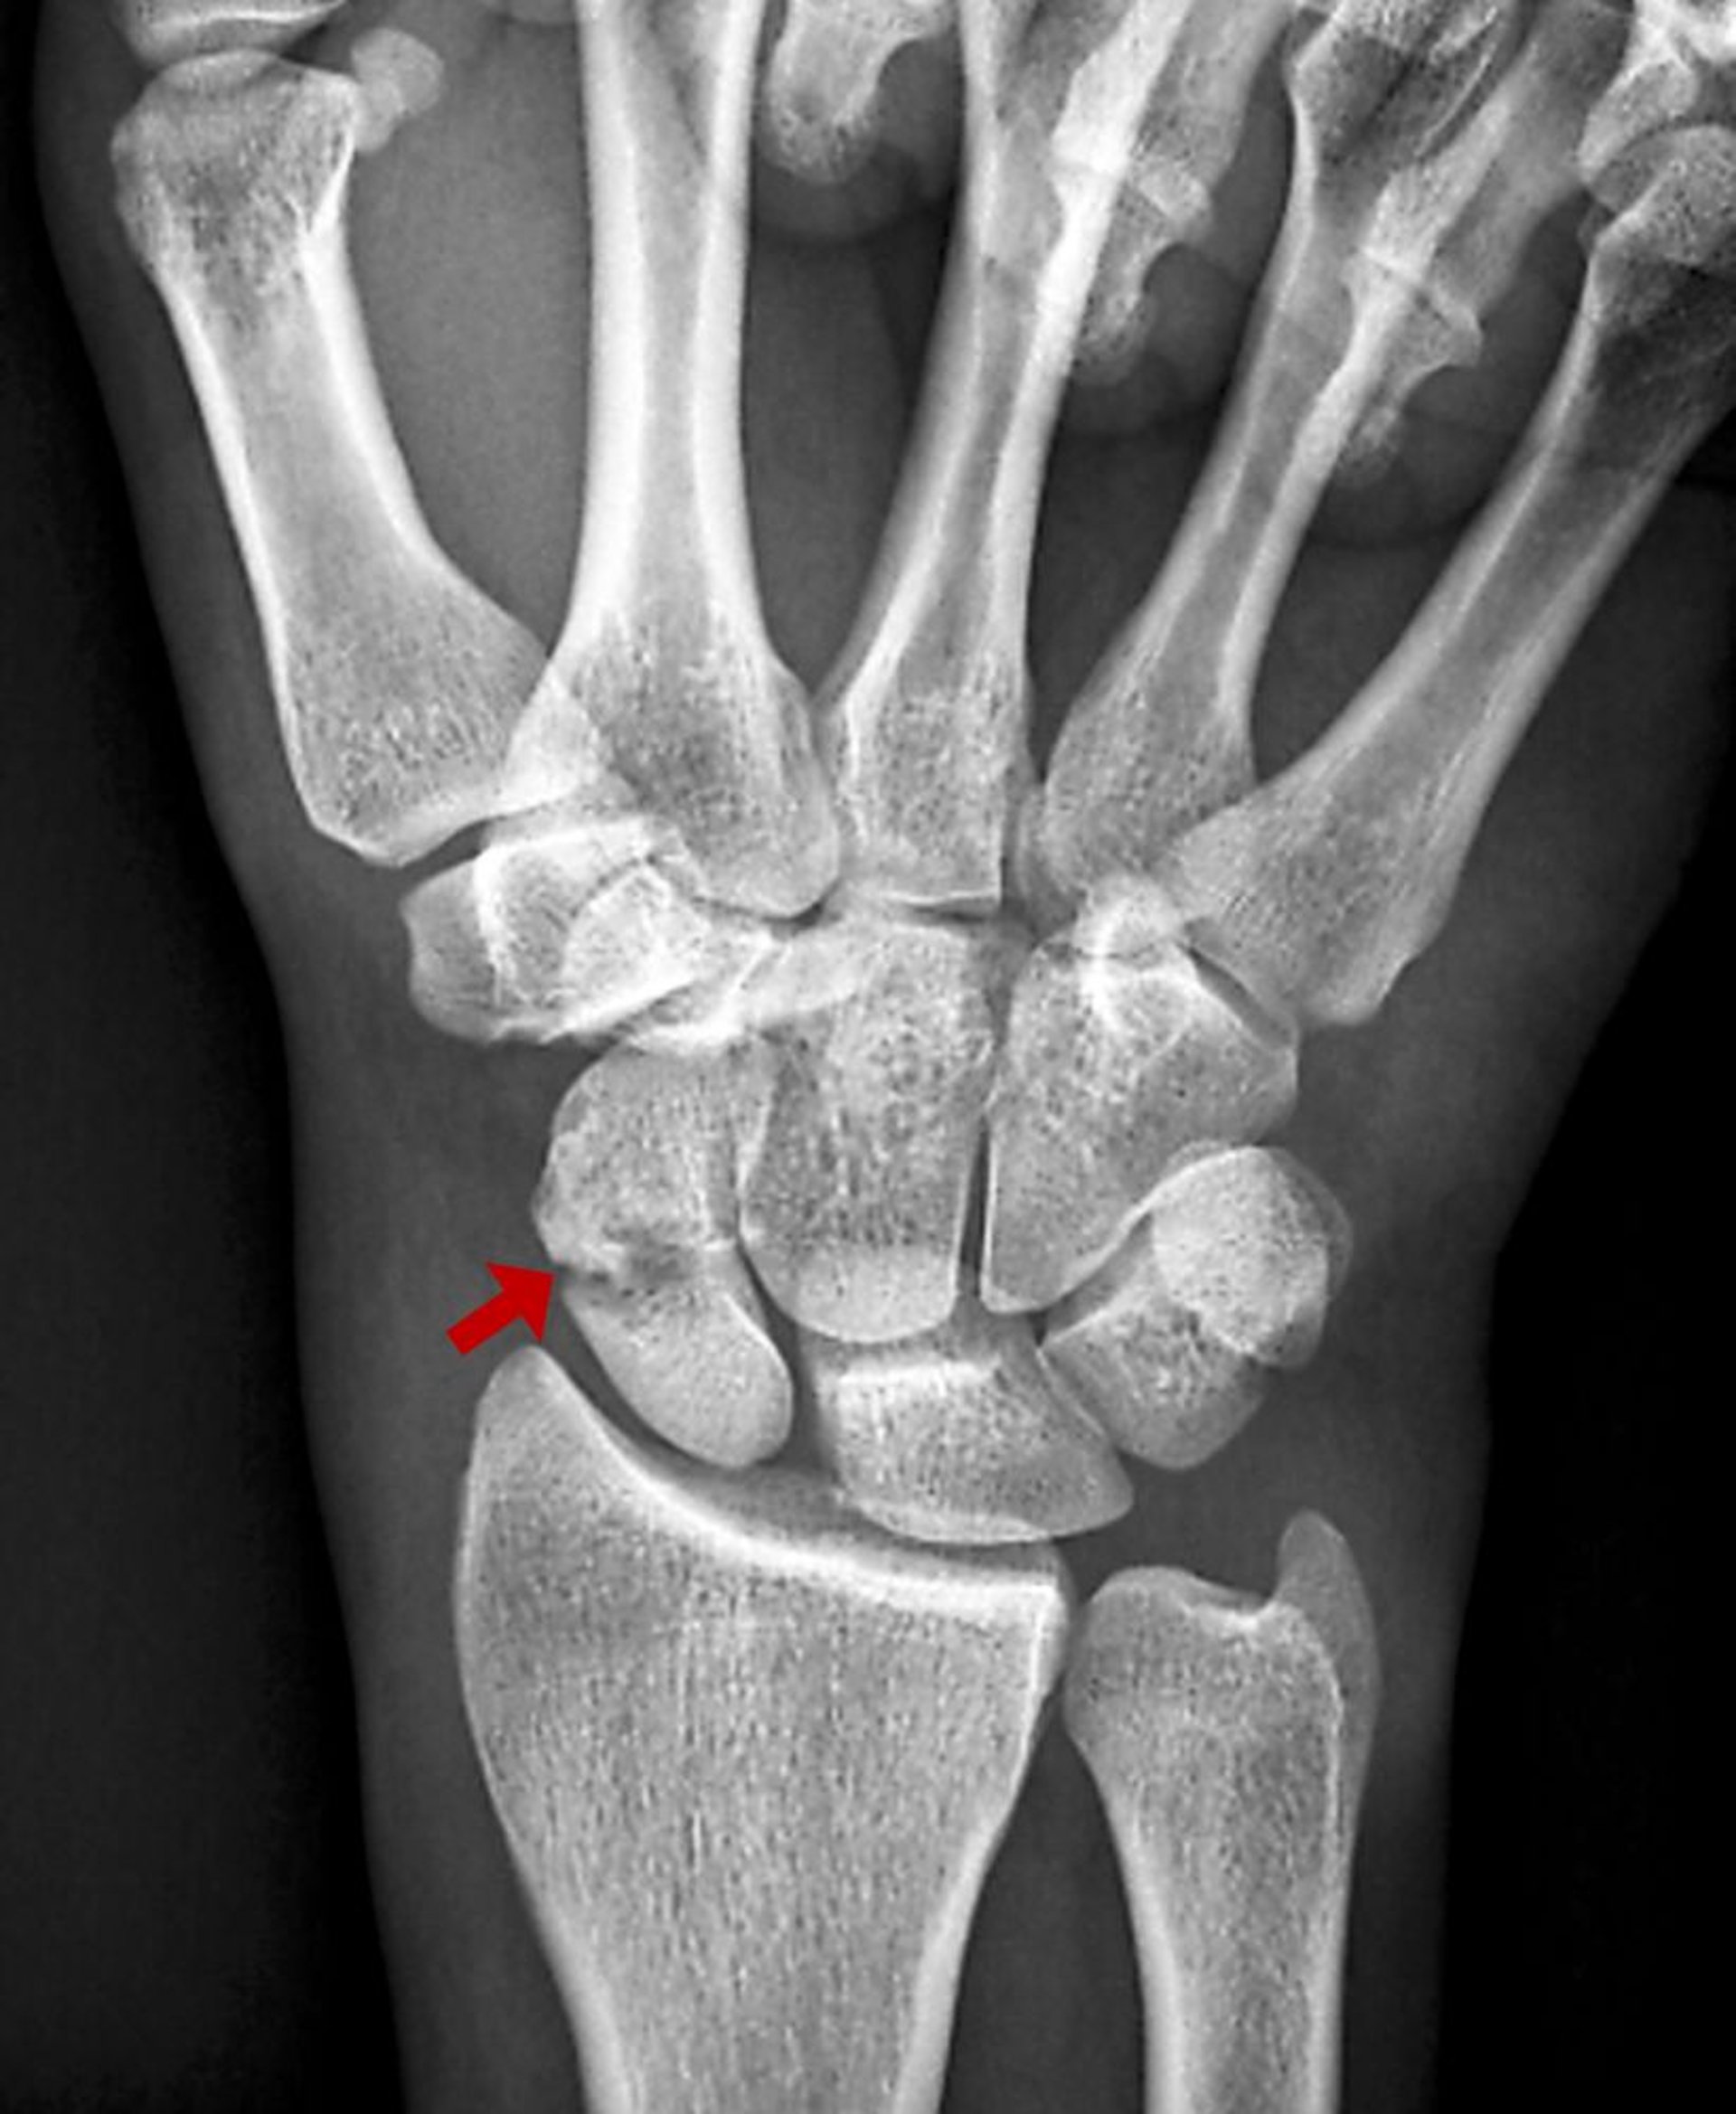

Перелом човноподібної кістки

Даний перелом човноподібної кістки візуалізується у вигляді зони просвітлення на звичайній рентгенограмі.